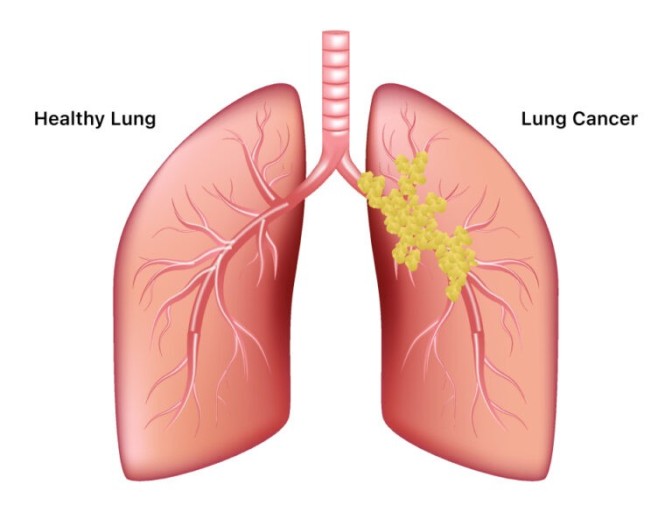

폐암은 위암, 갑상선암 다음으로 3번째로 발병 빈도가 높은 3대 암 중 한 가지입니다. 폐암은 재발과 전이까지의 빈도도 잦은지라 완치가 어렵다고 하며 폐암 발병 초기에는 거의 증상이 없을 수가 있어 수술이 불가능한 3기, 혹은 4기에 주로 진단된다고 합니다.

폐암 4기에 이르게 되면 5년 생존률이 30% 대로 떨어지게 된다고 합니다. 그리해서 폐암은 암 질병이자 중 사망자 비율이 가장 높은 것으로 나타나고 있습니다.

폐암은 사망률 2위를 차지하고 있는 간암에 비해 무려 2배에 가까운 사망률을 보이고 있다고 해요. 이렇게 치명적인 폐암에 대해 미리 알고 대처하는 것이 바람직할 것 같습니다. 아래에서는 폐암이라 판단해 볼 수 있는 그 초기증상에 대해 간단히 설명드리겠습니다.